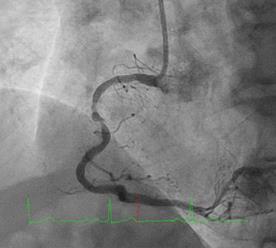

Can thiệp ngã ba động mạch liên thất trước và nhánh chéo 1 với hai stent có bọc thuốc bằng kĩ thuật cullote. Tiếp tục can thiệp động mạch vành phải với ống thông can thiệp (guiding catheter) (Cordis JR4 cm 6Fr) và dây dẫn (Asahi Sion 0.014”). Nong tổn thương bằng bóng 3.5 x 15mm (Neich Sapphire), bóng 4.0 x 12 (NC Quantum Apex), bóng cắt 3.5 x 15 (Cutting balloon, Angiosculpt) không làm vỡ được mảng vữa xơ. Quyết định dùng hệ thống khoan cắt mảng vữa xơ với dây dẫn mềm (Boston Scientific Rotablator Rotalink Plus) và mũi khoan (burr) 1.5mm. Tuy nhiên vì kích thước động mạch quá lớn nên mũi khoan đi qua tổn thương mà không chạm vào mảng vữa xơ được. Chuyển sang mũi khoan có đường kính lớn hơn 2.15mm với tốc độ khoan 150000 vòng /phút. Khi mũi khoa đi qua được 1/3 tổn thương thì không thể di chuyển được tiếp. Nhận định tại thời điểm đó là mũi khoan bị kẹt trong tổn thương tại đoạn giữa của động mạch vành phải. Ngay lập tức các bác sỹ có kinh nghiệm can thiệp trong bệnh viện được mời đến phòng can thiệp đồng thời thông báo cho các phẫu thuật viên tim mạch chuẩn bị trong trường hợp cần thiết. Bệnh nhân có biểu hiện đau tức ngực trái, tuy nhiên mạch và huyết áp tương đối ổn định, điện tim không thay đổi. Dòng chảy trong động mạch vành còn duy trì nhưng chậm TIMI 2. Sau khi hội ý, hướng xử trí đầu tiên là dùng dây dẫn cứng Conquest Pro (Asahi) để đi qua tổn thương nhưng không thành công. Sau đó chúng tôi quyết định cắt đoạn đầu của hệ thống nối mũi khoan, đưa ống thông heartrail (Terumo) sát vào mũi khoan nhằm thay đổi tư thế và cố định mũi khoan vào dây dẫn để đưa ra ngoài. Cuối cùng mũi khoan được đưa ra ngoài thành công. Tổn thương tiếp tục được nong bằng bóng cắt và bóng áp lực cao và đặt được giá đỡ kim loại (stent) bọc thuốc 4.0 x 26mm. Kết quả là động mạch vành được mở rộng hoàn toàn, bệnh nhân không còn đau ngực, huyết động ổn định.

Hình 1: A- hình ảnh động mạch vành trước can thiệp; B – dùng bóng cắt (cutting balloon) không phá vỡ được cấu trúc mảng vữa xơ; C – mũi khoan 1.5 không chạm vào được mảng vữa xơ vôi hóa; D – mũi khoan 2.15 bị tắc tại vị trí hẹp.